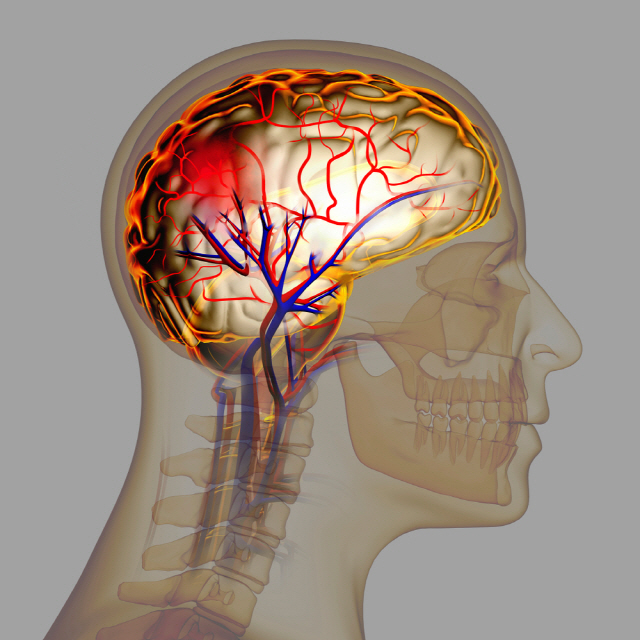

고혈압은 뇌출혈의 가장 큰 원인으로 볼 수 있는데 고혈압 환자라면 혈압이 갑작스럽게 상승하는데 이 때 산소와 영양소가 뇌로 들어가는 통로인 혈관에 변화를 일으키는데 혈관이 버티지 못하고 터지게 됩니다. 뇌동정맥의 기형에 의한 뇌출혈, 뇌동맥류 파열에 의하여 나타나며 잦은 흡연이나 다른 질병의 합병증으로 인해 발생할 수 있으며 뇌손상은 팔, 다리, 심하면 얼굴등 신체 일부분이 평생 마비시키며, 골든타임을 놓칠 경우 사망할 수도 있어 뇌출혈 전조증상에 대해 알고 있는 것이 좋습니다.

뇌출혈 전조증상 두 번째는 마비 증상과 동반한 구토 및 메스꺼움입니다. 뇌 출혈이 우뇌에서 생기는 경우 왼쪽에서 마비가 좌뇌에서 생기는 경우 우측에서 마비가 생길 수 있으며 이와 동반하여 어지러움, 메스꺼움, 구토 등의 증상이 나타날 수 있는데 이러한 증상은 혈압 상승으로 인해 기온이 떨어지는 겨울철에 발생하기 쉽습니다.

뇌출혈 전조증상 세 번째는 시력과 균형감각의 상실을 이야기 할 수 있습니다. 뇌 혈관 문제로 생기는 뇌출혈은 시신경과 관련하여 시야가 흐려지고 눈을 정상적으로 뜨기 어렵기 때문에 시력을 이부 상실할 수 있으며 균형 감각도 둔해져 가만히 있더라도 몸이 계속 기울어져 넘어질 수 있습니다.